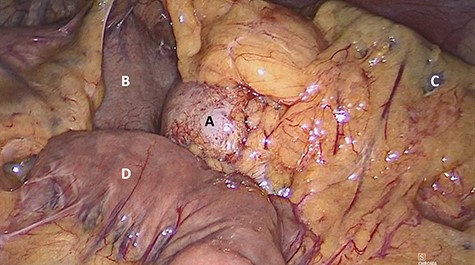

The patient underwent laparoscopic distal pancreatectomy with splenectomy (Figs 7 and 8) with the same surgical team. The patient had an uneventful postoperative recovery and was discharged within 48 hours.

Laparoscopic view of (A) nodular lesion, (B) vessel loop encircling the pancreas and (C) spleen.